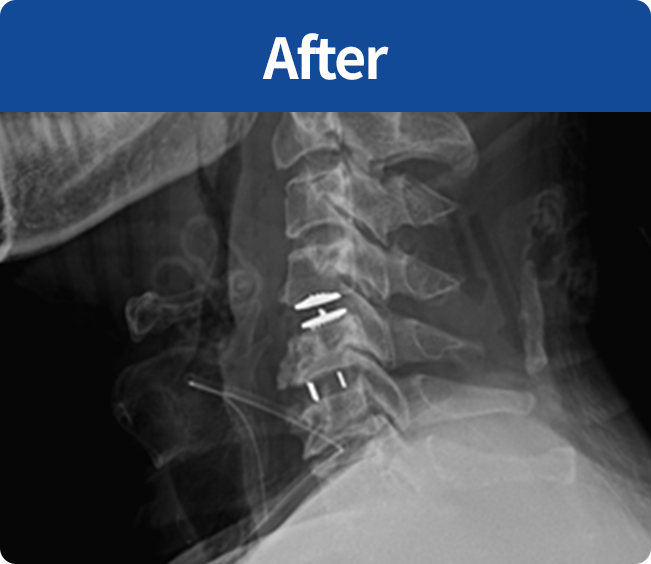

척추유합술

미세현미경을 통해

손상된 뼈와 인대조직을 제거하고 디스크의 역할을

해줄 인조 케이지를 삽입해 불안정한 척추체를

나사못으로 고정하는 수술

(척추 전방 골유합술, 척추 후방골유합술)

미세현미경을 통해 손상된 뼈와 인대조직을 제거하고 디스크의 역할을 해줄 인조 케이지를 삽입해

불안정한 척추체를 나사못으로 고정하는 수술 (척추 전방 골유합술, 척추 후방골유합술)